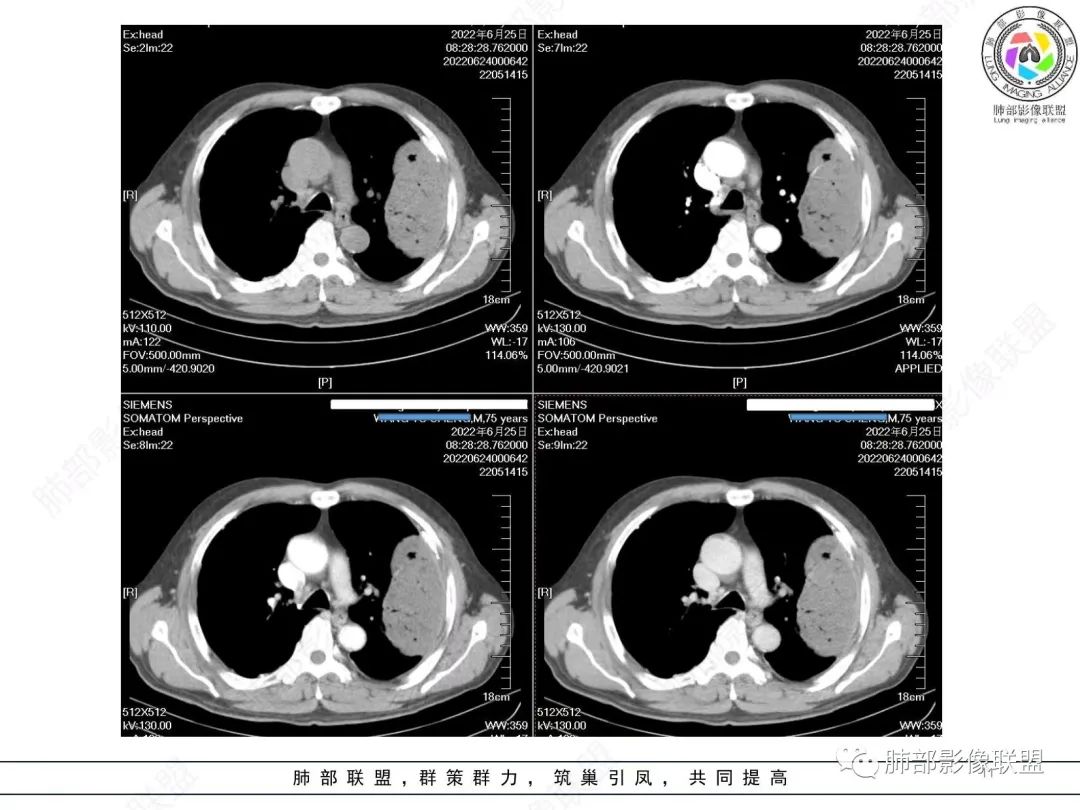

左肺上叶大肿块,膨胀性生长,边界清,密度较低,见部分坏死区,强化弱,肿块见支气管充气V扩张征,分布僵直,枯树枝特点,另一个重要特点血管造影征,淋巴瘤,肿块长轴与胸膜平行,与隐球菌鉴别,隐球荚膜抗原检查,明确诊断经皮肺穿刺。另胸膜钙化(问诊既往有无患胸膜炎病史)。

老年男性,糖尿病病史,消瘦、乏力三个月,影像表现左肺上叶胸膜下团块,有一定张力,内部疏松,可见支气管影及坏死区,增强病灶边缘环形强化,内部未见强化,考虑炎性肉芽肿病变,隐球?奴卡?放线菌?鉴别淋巴瘤。

左肺上叶胸膜下肿块,宽基底与胸膜相连,跨叶裂,边缘清晰膨隆,其内支气管充气,部分扩张、僵直,无明显强化,血管造影征,考虑淋巴瘤,鉴别腺癌

左肺胸膜下巨大占位,跨叶裂,宽基底与胸膜相连,胸膜钙化,平扫密度较低,强化不明显,可见内部血管显影,支气管充气征和扩张,考虑为恶性,倾向于淋巴瘤

左侧胸腔巨大肿块,跨叶生长,临近胸膜钙化,边缘模糊,可见支气管影,定位肺内,增强后轻度强化,边缘见血管影,考虑淋巴瘤,鉴别肉瘤

左肺上叶胸膜下肿块,膨胀性生长,边界清晰,密度不均部分坏死,未见强化,病灶内支气管迂曲扩张,病灶长轴与胸膜平行,胸膜下脂肪间隙存在,胸膜钙化,考虑放线菌?毛霉?鉴别淋巴瘤

支持淋巴瘤,左上肺大肿块,有分叶,边缘光整,病灶内密度不均,可见支气管扩张征,增强后可见血管影征。周围肺野清晰。

左肺上叶肿块,宽基底与胸膜相连,跨叶裂,边缘清晰膨隆,可见小分叶,其内支气管充气,部分扩张、僵直,呈枯枝征,支气管达边征,增强无明显强化,可见血管造影征,考虑恶性病变,淋巴瘤,鉴别粘液腺癌。

糖尿病史,慢性病程,左肺巨大肿块,跨叶生长,肿块近端可见充气支气管征及悬浮气泡,轻度圴匀强化,病变长轴与胸膜平行,炎性标志物正常,考虑放线菌,其次淋巴瘤

我要修正一下观点了:仔细看了视频,肿块占位效应明显,对周围血管,支气管有推挤,增强后强化不明显,NSE增高,半年体重下降25公斤,虽然有内部支气管扩张,血管漂浮,边界清楚支持淋巴瘤,但强化太低,膨隆,占位推挤太明显(淋巴瘤一般没有这么明显的占位效应),胸膜关系有载桩,恶病质明显(乏力,半年体重下降了25公斤),NSE也明显增高,就不支持淋巴瘤了。还是考虑外朝内的恶性肿瘤,间质来源的肉瘤伴有神经内分泌分化或者大神泌。

不支持淋巴瘤的有四点:1、对周围血管支气管推挤明显。2、胸膜有栽桩,3、强化太弱(淋巴瘤一般还是中度以上甚至高度强化多见),4、NSE升高明显,体重下降太明显。

老年男性,糖尿病病史,消瘦、乏力三个月,肿瘤标志物高。左肺上叶胸膜下肿块,边界清晰,可见支气管影及坏死区,增强病灶边缘强化,内部未见明显强化,邻近胸膜有累及,考虑恶性,建议穿刺活检。

左肺紧贴胸膜巨大肿块,跨叶裂生长,密度均匀,边缘清晰,内支气管略扩张,增强见血管影,强化不明显,胸膜栽赃,钙化,考虑淋巴瘤。